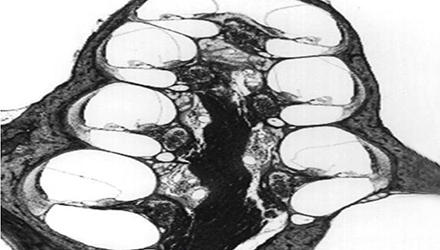

膜迷路积水致膜迷路胀破,内外淋巴液混合,刺激神经感觉细胞导致眩晕、耳鸣、耳聋,裂口愈合则病变暂时恢复。下图左为前庭膜膨大,右图为前庭膜破裂,内外淋巴交混。